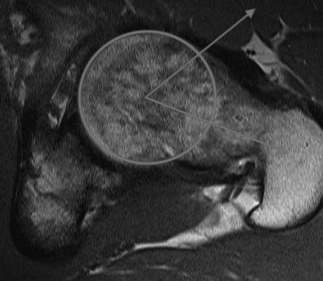

MRI

MRI alpha angle

CT

Cam impingement